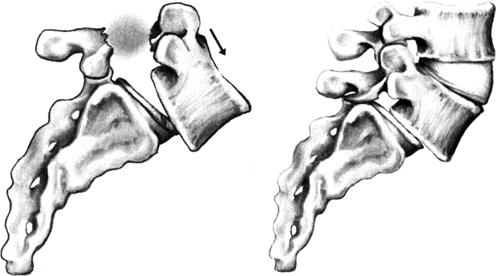

脊柱各部分的连接复杂而多样化,既要维持脊柱的稳定,又要使各部分有充分灵活的运动,以应付各种生理活动的需要。椎间关节是重要稳定结构,但其功能随部位而异。颈段椎间关节接近水平位,可在各方向运动,特别是旋转,因此很少参与脊柱的稳定。在下腰段,椎间关节近似直立,屈曲伸直自如,侧屈稍受限,但几乎无旋转。此处脱位多合并关节突骨折。椎间关节退变可使椎间盘承受更多剪应力,引起脊椎滑脱。在下胸段和上腰段,椎间关节方向处于中间位,属于过渡型。此处活动范围较大,如棘间韧带断裂,可发生脱位。

脊柱连接由韧带、椎间盘及椎间关节构成(图1-25)。

图1-25 脊柱的连接